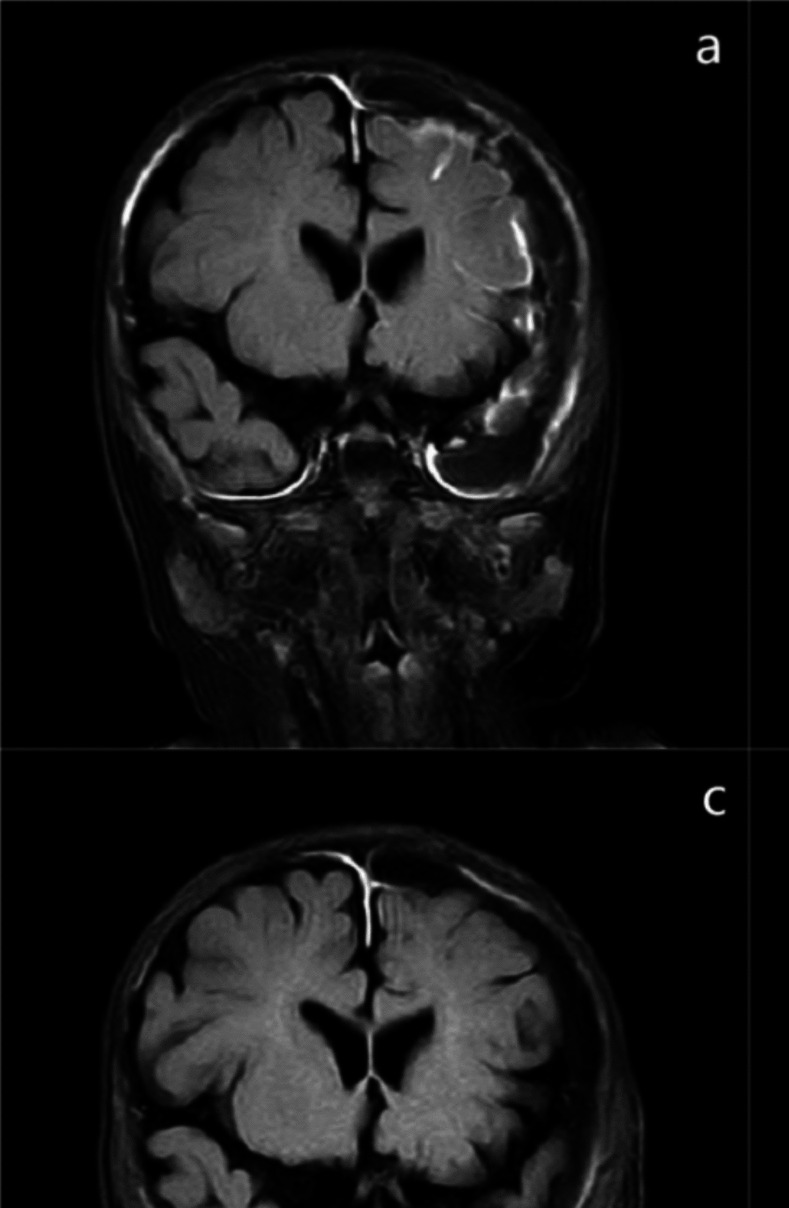

这一病例报告提出了一种新的治疗方法难治性化脓性脑膜炎在1个月的婴儿引起青霉素敏感的B组链球菌。尽管最初给予静脉注射抗生素治疗,包括青霉素和万古霉素,婴儿仍出现持续症状和双侧硬膜下积液。传统的治疗方法不能解决这些问题,导致使用一种新的技术:经前囟门的蛛网膜下腔穿刺联合鞘内万古霉素。这种微创手术允许靶向抗生素递送,显著减少硬膜下积液并改善脑脊液参数。患儿临床表现明显改善,68天后出院,随访3个月无并发症。尽管需要进一步的研究来证实其在更广泛的临床背景下的有效性和安全性,但这种方法为诸如开颅术或硬膜下外引流等更具侵入性的治疗提供了一种有希望的替代方法。

This case report presents a novel treatment approach for refractory purulent meningitis in a 1-month-old infant caused by penicillin-sensitive group B Streptococcus. Despite initial treatment with intravenous antibiotics, including penicillin and vancomycin, the infant experienced persistent symptoms and bilateral subdural effusions. Conventional therapies failed to resolve these issues, leading to the use of a new technique: subarachnoid puncture via the anterior fontanelle combined with intrathecal vancomycin administration. This minimally invasive procedure allowed for targeted antibiotic delivery, significantly reducing subdural effusions and improving cerebrospinal fluid parameters. The infant showed substantial clinical improvement and was discharged after 68 days with no complications during a 3-month follow-up. This approach offers a promising alternative to more invasive treatments such as craniotomy or subdural external drainage, though further research is needed to confirm its efficacy and safety in broader clinical contexts.